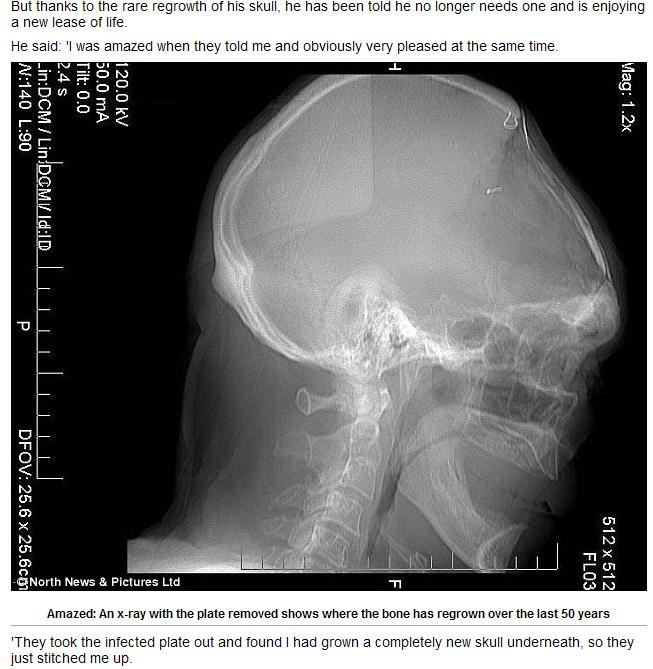

Numai ca in august, atunci cand Gordon Moore a ajuns pe masa de operatie, doctorii au facut o descoperire uluitoare: osul crescuse la loc si din aceasta cauza placa se miscase si ii crease rana, scrie DailyMail.

Si nu este vorba de numai cativa centimetri de os regenerat. Craniul a crescut la loc de la sprancene pana in varful capului. Asa ca nu a mai fost nevoie ca barbatul, care acum este strabunic, sa astepte luni de zile pentru o noua placa metalica.